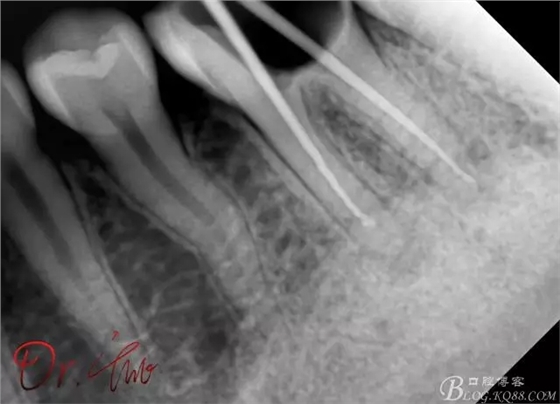

重點第二例病例,初診

拍片確定長度

試主尖,近中頰側(cè)形成臺階

試主尖,近中頰側(cè)再次拍片查看臺階位置及確定長度